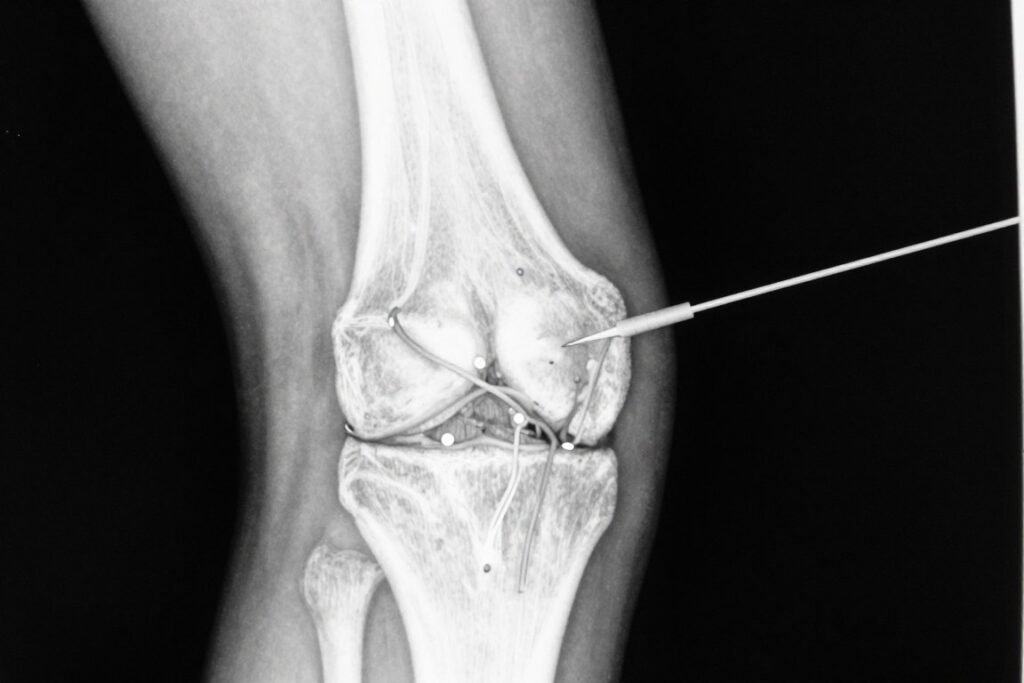

Fluoroscopy image showing proper needle placement for genicular nerve ablation

- Using fluoroscopy guidance, special radiofrequency cannulas (needles) will be inserted near the targeted genicular nerves.

- Sensory testing will be performed to confirm proper needle placement.

- Motor testing will ensure no unwanted motor nerve stimulation.